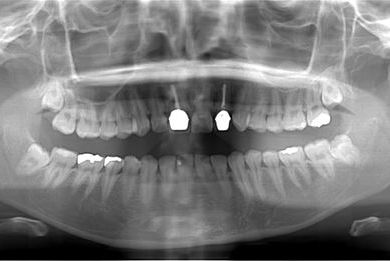

| 性別/年齢 | 女性 / 21歳 | ||||||||||||||||||||||||||||||||

| 主訴 | 現在、金属の入っている歯が虫歯になっているようなので、治してセラミックにしたい。 | ||||||||||||||||||||||||||||||||

| 治療方針 | セラミック治療にて審美的回復を行う。 | ||||||||||||||||||||||||||||||||

| 治療内容 | ハイブリッドセラミックインレー6本 | ||||||||||||||||||||||||||||||||

| 総治療費 | 189,000円 | ||||||||||||||||||||||||||||||||

| 治療期間 | 3ヶ月 |